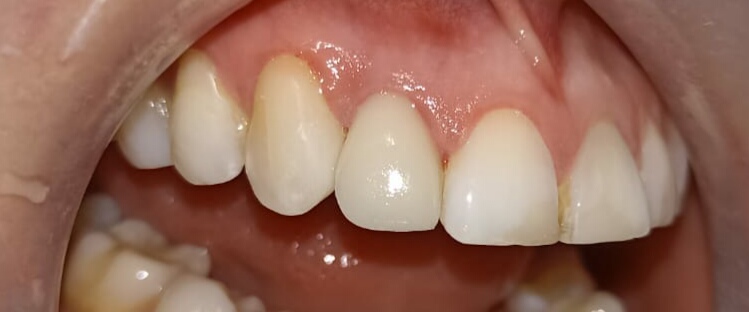

Coronas libres de metal en Quito: estética, resistencia y naturalidad para tu sonrisa

Cuando un diente está fracturado, debilitado o ha sido tratado con endodoncia, una de las…